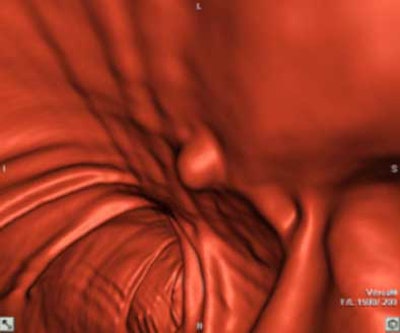

| Top to bottom: A 10-mm polyp in the splenic flexure can be seen in axial, sagittal, coronal, and 3D views. All images courtesy of Dr. Riccardo Iannaccone, University of Rome "La Sapienza." |